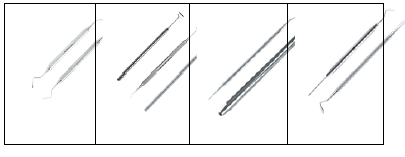

Considere as imagens abaixo na sequência:

Os instrumentais indicados representados na figura, são:

Assinale a alternativa CORRETA: